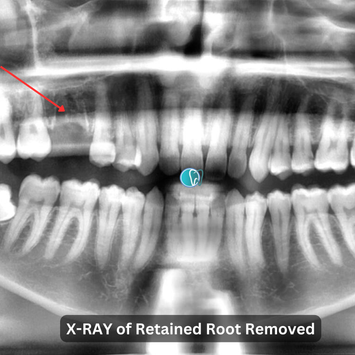

Surgical Removal of Retained Roots #16

Tooth #16: Gross caries with retained roots. Mobility and probing depth within normal limits (WNL). Slight metallic sound on percussion, indicating potential dense bone or ankylosis.

Fractured retained roots: Three roots identified—mesial buccal (mb) and palatal (p) roots are long, wide, flattened, and jointed; distal buccal (db) root is separated.

A CBCT scan was taken to evaluate the retained roots and surrounding structures. Risks of oroantral perforation (OAP) and oroantral fistula (OAF) were discussed with the patient, who understood and provided informed consent.

A post-operative CBCT scan confirmed no remnants of the extracted roots, with the maxillary sinus and adjacent teeth unaffected.